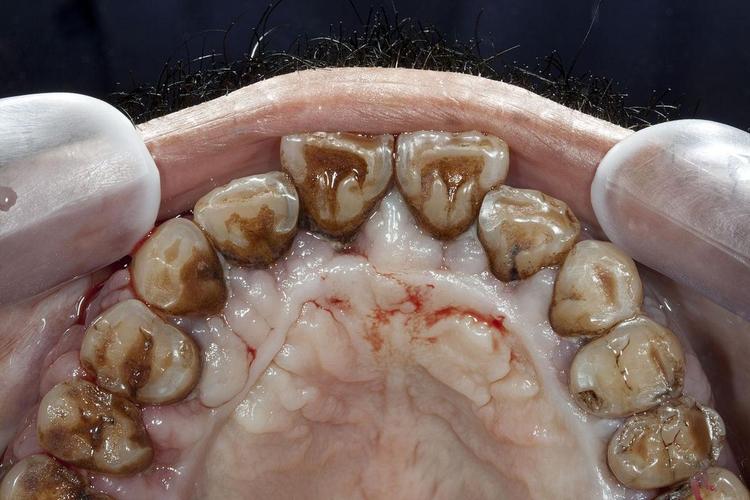

- 牙龈组织健康问题: 重度牙周炎常伴随牙龈退缩、牙周袋深、牙龈炎症明显,健康的牙龈组织对于封闭种植体颈部、防止细菌入侵至关重要,炎症的牙龈组织难以形成良好的生物学封闭。

- 龈上洁治: 清除牙齿表面菌斑和结石。

- 龈下刮治和根面平整: 清除牙周袋内和牙根表面的菌斑、结石和病变牙骨质,这是控制炎症、阻止骨吸收进展的关键步骤。

- 牙龈没有明显红肿、出血。

- 牙周袋深度在可接受范围内(lt;5mm)。

- 没有活动性骨吸收。

- 患者能很好地维护口腔卫生。